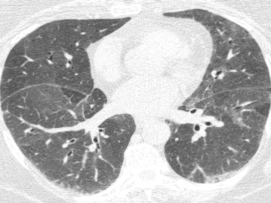

这位慢性纤维化型过敏性肺炎患者就可以看到三种密度征、磨玻璃影、网格影、牵拉性支气管扩张,没有蜂窝。

ero为什么不显示叶俏教授:HRCT是发现和鉴别「过敏性肺炎」的重要环节,何种表现指向预后不良?使患者发病的危害因素躲在哪些环境中?_https://www.jmylbn.com_新闻资讯_第38张

病例:女,59岁,鸽子肺,GGO+网格影+囊腔:

ero为什么不显示叶俏教授:HRCT是发现和鉴别「过敏性肺炎」的重要环节,何种表现指向预后不良?使患者发病的危害因素躲在哪些环境中?_https://www.jmylbn.com_新闻资讯_第41张